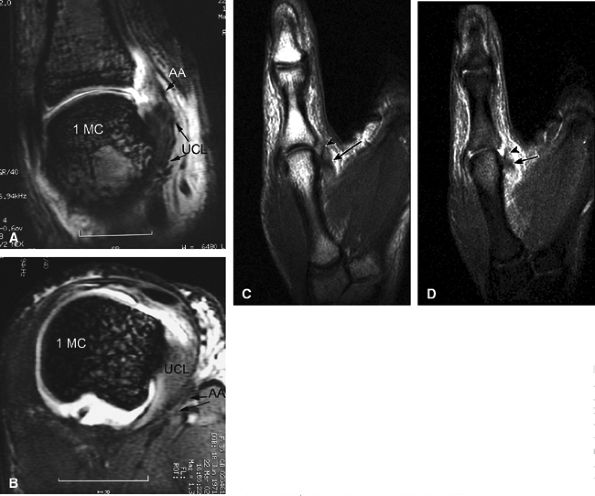

rotation. Stability is provided by the collateral ligaments, the volar plate, and musculotendinous elements. When the sesamoid bones are included in the volar plate, it is referred to as the volar complex (Fig. 11.4). On the medial aspect of the joint, the adductor pollicis is a strong insertion on the proximal phalanx and the volar plate, and contributes to the adductor aponeurosis. The ulnar collateral ligament (UCL) is covered dorsally by the adductor aponeurosis (Fig. 11.5).7,13

FIGURE 11.5 ● Coronal (A) and axial (B) T1-weighted images showing the ulnar collateral ligament (UCL) and adductor aponeurosis (AA). The UCL is deeper than the AA on axial images. On coronal images, the oblique AA is often more visible distal to the UCL. MC, metacarpal; PP, proximal phalanx.

|

The UCL lies deep to the overlying low-signal adductor aponeurosis on coronal images (Figs. 11.7 and Fig. 11.8). In a nondisplaced partial or complete tear of the UCL, the ligament appears thickened all along its course, sometimes with a small gap. When displaced, the UCL appears as a proximally retracted round or stump-like structure, which demonstrates low signal on all sequences. It is no longer parallel to the long axis of the thumb and presents an increased horizontal orientation.

On axial images, the ligament may be seen lying above or intersecting the adductor aponeurosis.